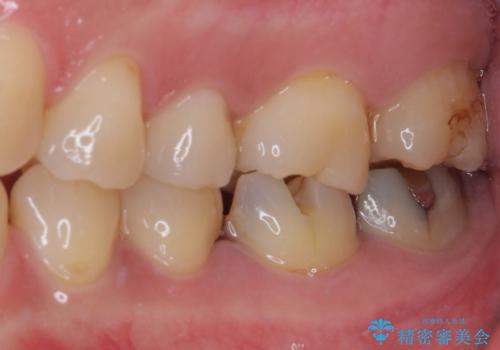

奥歯は虫歯が放置されていましたが、特に症状はなく歯髄の状態も正常でした。

前歯、奥歯ともにオールセラミッククラウンやセラミックインレーにて治療を行うこととしました。